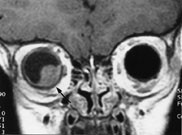

Melanomer gir karakteristisk signal fordi melanocyttene kan være paramagnetiske og gi høy signalintensitet på T1-vektede og lav signalintensitet på T2-vektede MR-bilder. Dette er karakteristisk, men mangler hos ca. 5 %. Postkontrast-T1-bilder med fettsuppresjon eller SPIR-teknikk er best egnet til å påvise små uveale melanomer (8) (fig 5).

Ekstraokulær utbredelse av uvealt melanom sees som et velavgrenset område med lav signalintensitet på T1-bilder, men med normal eller lav signalintensitet på T2-bilder i forhold til det orbitale fettet. Etter kontrast fremkommer bare moderat oppladning. MR er nyttig for å skille mellom en ekstraokulær ekspansjon og et ikke-oppladende fibrotisk arr i nær relasjon til sclera etter lokal stråleterapi.